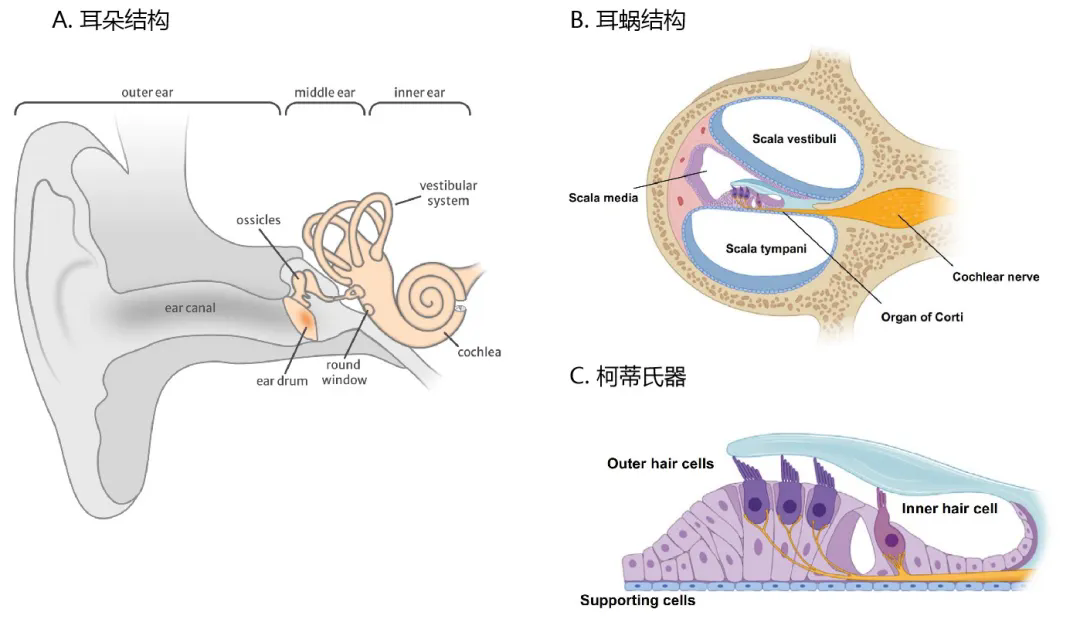

耳朵結構

耳(er)(er)(er)朵分為外耳(er)(er)(er)、中耳(er)(er)(er)和(he)內(nei)(nei)耳(er)(er)(er)三部分,其中外耳(er)(er)(er)和(he)中耳(er)(er)(er)傳導聲波(bo),內(nei)(nei)耳(er)(er)(er)是聽覺(jue)和(he)位(wei)覺(jue)感受(shou)器。在結構上(shang),外耳(er)(er)(er)包(bao)括(kuo)耳(er)(er)(er)廓和(he)外耳(er)(er)(er)道,中耳(er)(er)(er)由鼓膜(mo)、鼓室及聽骨鏈組成(cheng),內(nei)(nei)耳(er)(er)(er)位(wei)于(yu)顳骨巖部內(nei)(nei),包(bao)括(kuo)半規管、前庭和(he)耳(er)(er)(er)蝸(cochlea)。值得注意的(de)(de)是,大多數引起耳(er)(er)(er)聾的(de)(de)基因主要在耳(er)(er)(er)蝸內(nei)(nei)的(de)(de)細胞中表達,因此(ci),AAV介(jie)導的(de)(de)針對(dui)聽力損失(shi)的(de)(de)基因療(liao)法一般(ban)都(����dou)集中于(yu)靶(ba)向耳(er)(er)(er)蝸結構。

哺乳(ru)動(dong)物的(de)耳蝸(gua)(gua)內(nei)含有兩種類型的(de)毛(mao)細(xi)胞(bao)(bao)(bao)(bao)(Hair Cells, HCs):內(nei)毛(mao)細(xi)胞(bao)(bao)(bao)(bao)(IHCs)和外毛(mao)細(xi)胞(bao)(bao)(bao)(bao)(OHCs),這兩種毛(mao)細(xi)胞(bao)(bao)(bao)(bao)對(dui)聽(ting)覺信號(hao)的(de)檢測和處(chu)理至關(guan)重(zhong)(zhong)要(yao),成熟的(de)哺乳(ru)動(dong)物毛(mao)細(xi)胞(ba������o)(bao)(bao)(bao)不(bu)能再生(sheng),因此這些細(xi)胞(bao)(bao)(bao)(bao)一旦(dan)發生(sheng)損傷,其退化過程往(wang)往(wang)是不(bu)可逆(ni)的(de)。支持(chi)細(xi)胞(bao)(bao)(bao)(bao)(Supporting cells, SCs)圍繞在毛(mao)細(xi)胞(bao)(bao)(bao)(bao)外周,對(dui)耳蝸(gua)(gua)內(nei)穩態十分重(zhong)(zhong)要(yao),引(yin)起先(xian)天性(xing)耳聾的(de)GJB2基因即在支持(chi)細(xi)胞(bao)(bao)(bao)(bao)中表(biao)達。螺旋神經節神經元(yuan)(Spiral Ganglion Neurons, SGNs)是聽(ting)覺系統的(de)一級神經元(yuan),在聽(ting)覺傳導�����過程中起重(zhong)(zhong)要(yao)作用。

此外(wai),由(you)毛細胞(bao)、支持細胞(bao)及其它(ta)附屬結構構成了Corti器(柯蒂(di)氏器),Corti器周(zhou�������)圍是(shi)充滿外(wai)淋巴(ba)管的(de)前庭階(jie)(Scala vestibuli)、鼓階(jie)(Scala tympani)以及充滿內淋巴(ba)管的(de)蝸管(Scala������ media)。

圖1. 耳朵結構(gou)分(fen)析

(//www.audiocure.com/inner-ear-disorders/)

(Peters CW, et al. Trends Pharmacol Sci. 2021)